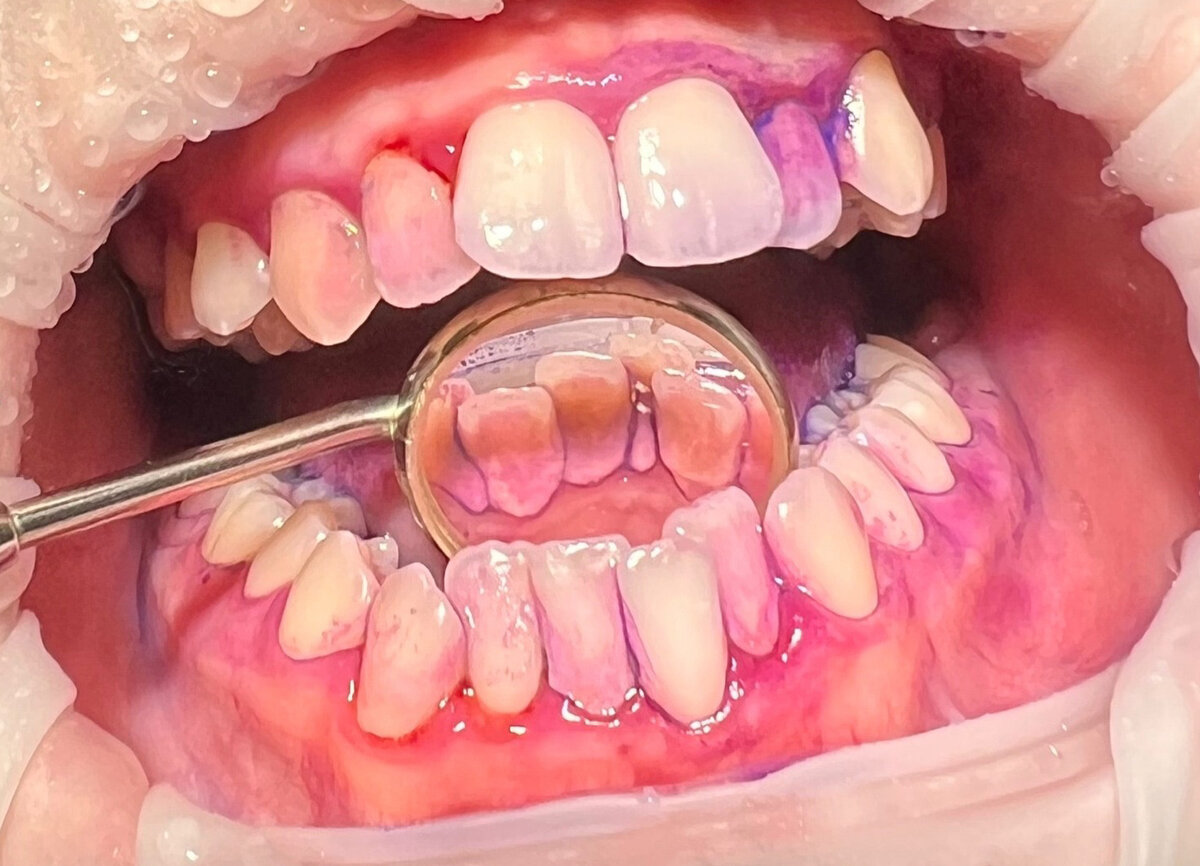

В отчете DIANA указана вся необходимая информация о гигиеническом состоянии полости рта пациента. Результаты анализа включают в себя количество налета, оценку индексов и снабжены фотографиями окрашенных зубов. Количество зубного налета указывается в процентном соотношении длительного и суточного налета. Индексы гигиены содержат референсные значения, понятные как врачу, так и стоматологу. История наблюдений позволяет отслеживать прогресс пациента, эффективность соблюдения рекомендаций и проводимых гигиенических мероприятий. Рекомендации дают возможность гигиенисту назначать дату следующего приема, а также советовать пациенту посетить врачей-стоматологов других специальностей при наличии показаний. Комментарий врача содержит информацию о необходимых назначениях, средствах гигиены и алгоритме действий после проведения процедуры профессиональной гигиены. Создание и сохранение шаблонов рекомендаций позволяет быстро назначать те или иные средства гигиены в зависимости от клинической картины

В отчете DIANA указана вся необходимая информация о гигиеническом состоянии полости рта пациента. Результаты анализа включают в себя количество налета, оценку индексов и снабжены фотографиями окрашенных зубов. Количество зубного налета указывается в процентном соотношении длительного и суточного налета. Индексы гигиены содержат референсные значения, понятные как врачу, так и стоматологу.